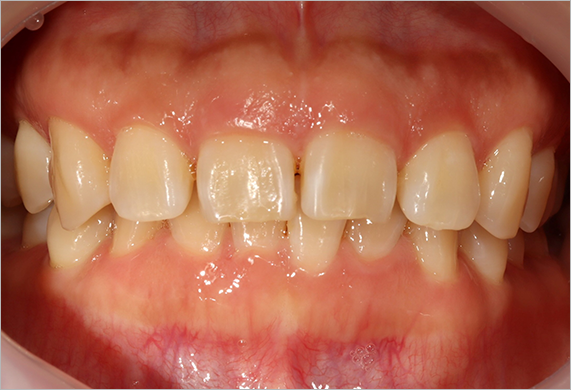

덧니 교정 CASE

-

연세바로치과는 치료법을 준수합니다. 로그인 하시면 Before를 보실 수 있습니다. LOGIN